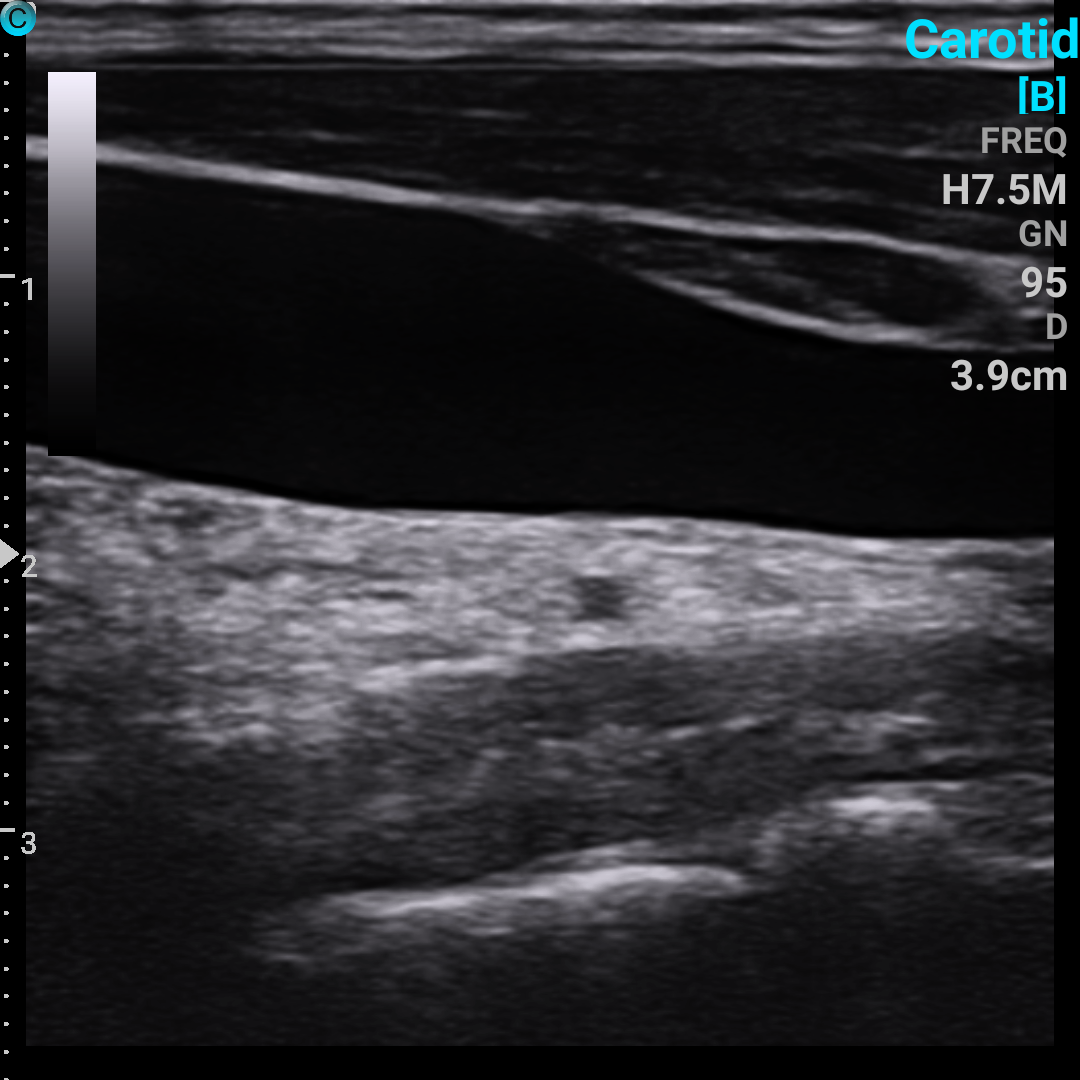

颈内静脉 B模式

颈动脉 PW模式